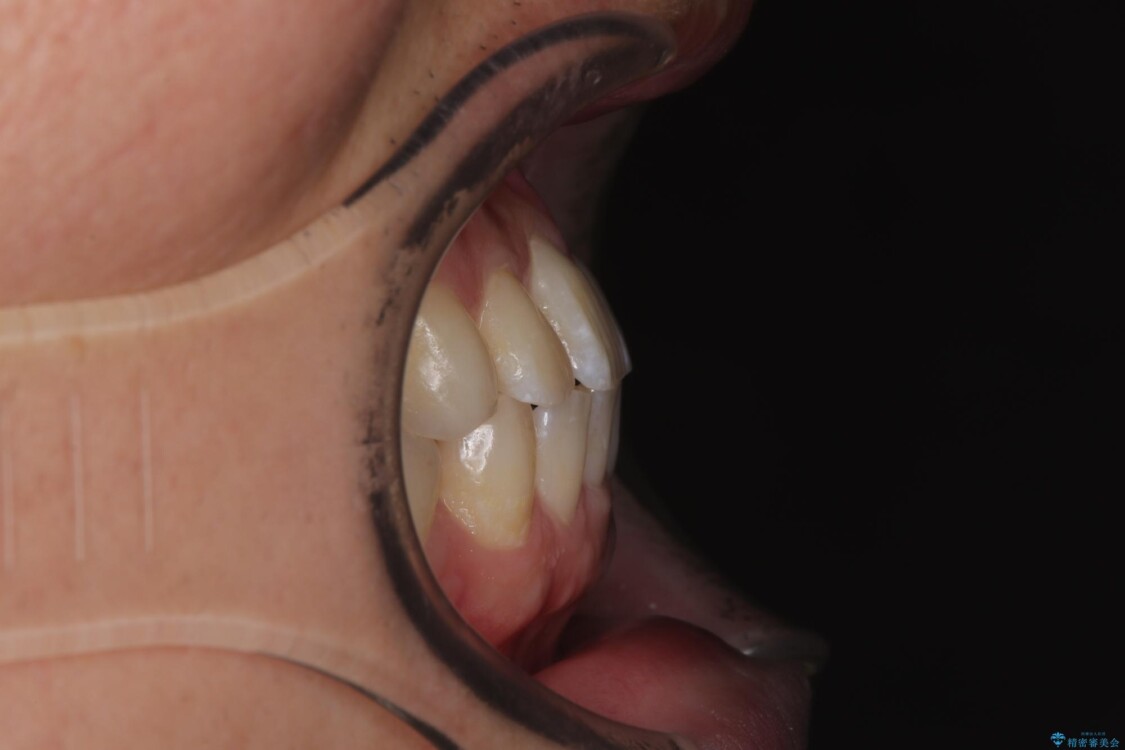

・上顎左右の第二大臼歯が頬側へ転移し、シザーズバイト(scissors bite)の状態

・上顎左側第二小臼歯が90度捻転しており、噛み合わせに影響

治療前

• 前歯のガタガタ・奥歯のかみ合わせ(シザーズバイト)を改善|1年半で完了したメタルブラケット矯正 治療前画像